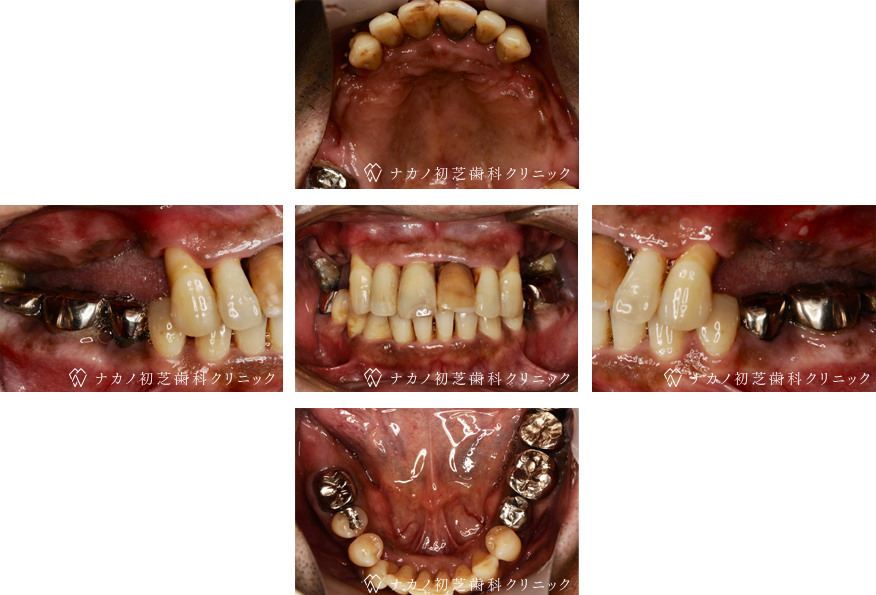

インプラント・13本 (60代女性)

BEFORE

AFTER

年齢 60代女性

治療内容 インプラント治療13本(骨造成の併用)

インプラント治療とは、歯を抜いた所にチタン製の人工歯根を埋入し、その上に歯を入れる方法です。骨を増やすことで、より審美的に治療が出来ました。費用 1本 400,000円(税込 440,000円)

リスク・副作用

腫れ・疼痛・違和感を感じるなどの症状を生じることがあります。